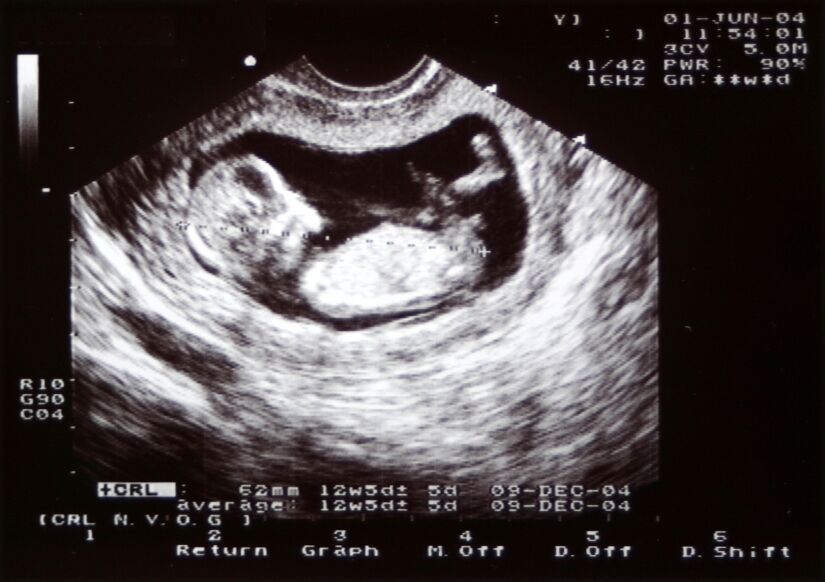

Newer ultrasound technology allows medical professionals to get a very detailed ultrasound image. High resolution ultrasounds as well as the new "3D" and "4D" ultrasounds can give you a really clear picture of your baby, almost like having a photograph of your new arrival before baby arrives! 3D ultrasounds generate a 3D still image of your baby while 4D ultrasounds create a 3D moving image of your baby.

During your first trimester, your baby may look like little more than a peanut to you. Rest assured that your healthcare providers can tell a lot by this tiny image. Ask them to point out the outline of your baby for you and to show you your baby's beating heart.